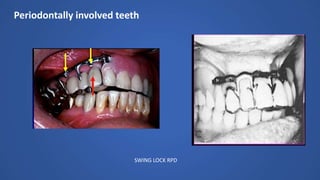

Periodontally involved teeth

SWING LOCK RPD